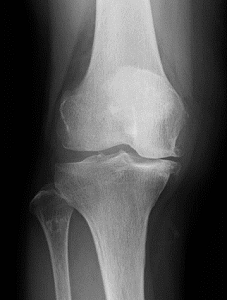

変形性膝関節症、関節リウマチ、外傷による後遺症などで、リハビリテーションや注射などの保存的な治療の効果が得られない状態までダメージを受けてしまった膝関節は、症状が回復する可能性が低く、日常生活が制限されるほどの非常に強い痛みを伴います。特に軟骨が完全に欠損してしまった場合は細胞治療などを行っても軟骨は完全には再生しないため効果は乏しいです。